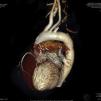

A 59-year-old woman with type 2 diabetes and two-vessel disease had undergone double coronary bypass grafting (CABG) five years previously, with left internal mammary artery (LIMA) to left anterior descending (LAD) artery and free radial graft (Y type), from LIMA to obtuse marginal (OM). Three months ago, the patient began to suffer angina and episodes of dizziness after upper limb exercise, followed by a lateral wall myocardial infarction one month ago. Urgent femoral catheterization revealed thrombotic occlusion of the circumflex (Cx) artery; the LAD had an old occlusion and the LIMA could not be catheterized. The right coronary artery (RCA) was normal. Primary angioplasty of the culprit Cx was performed and two bare-metal stents were deployed. The acute chest pain resolved, but angina and dyspnea recurred one week later. Physical examination revealed absent pulses in the left arm. Cardiac CT angiography revealed abrupt occlusion of the left subclavian artery 1.8cm after its origin, proximal to the LIMA and the ipsilateral vertebral artery. Both these arteries supplied a scant flow to the axillary artery (Figures 1 and 2), but the LIMA was well contrasted, with a good anastomosis to the mid LAD (Figures 1, 2 and 3a). The radial (LIMA to OM) anastomosis was totally occluded, only the path of the metal clips being visible (Figure 2). The Cx stent was patent with no signs of restenosis, and the RCA was normal (Figure 3b and c). The right brachiocephalic and left carotid arteries were normal (Figures 1 and 2). A triplex Doppler scan revealed reversal of left vertebral artery flow (Figure 4). A diagnosis of coronary-vertebral subclavian steal syndrome was made.

In this case, a large CT acquisition window was used, ranging from the middle neck region to the diaphragm, to ensure good anatomical coverage, particularly of the proximal supra-aortic vessels, in preparation for possible future surgery. Since the left carotid artery was disease-free, a carotid-left axillary shunt was proposed, without further invasive investigations.